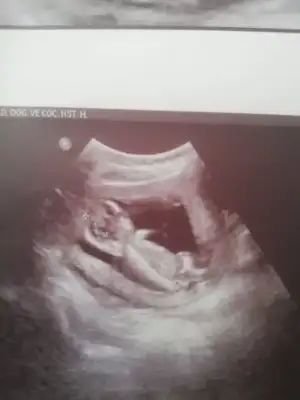

bunada bakabilirmisiniz 11 haftalık

o kadar fazla araştırdım ki bu nub olayını beynim yandı benimde..

ama sizin usg çok net belli.. tabi bendeki tahmin sadece.. 😄

kız diyorum bu nub için..

hatta çizimi şöyle..

tüm evlatlar hayırlı sağlıklı olsun inşallah..😊

Bir de bana bakın hanımlar 11 haftalık nedir sizce Havalianne__ Havalianne__